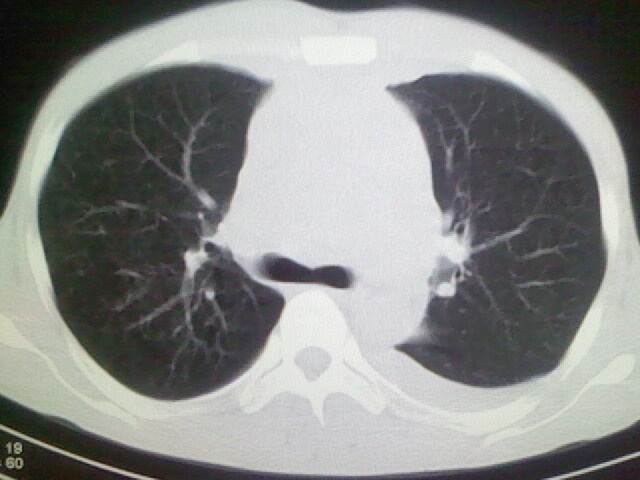

以下是引用杀毒软件在2008-9-3 6:11:00的发言:[br]侵袭性胸腺瘤------一般不侵到气管旁[br][br]考虑----纵隔淋巴瘤,心包及胸膜受累

以下是引用wzr在2008-9-3 5:30:00的发言:[br]侵袭性胸腺瘤

以下是引用随光逐影在2008-9-3 7:07:00的发言:[br]1)考虑淋巴瘤可能。2)双侧胸腔积液(以左侧为甚)。3)心包积液。